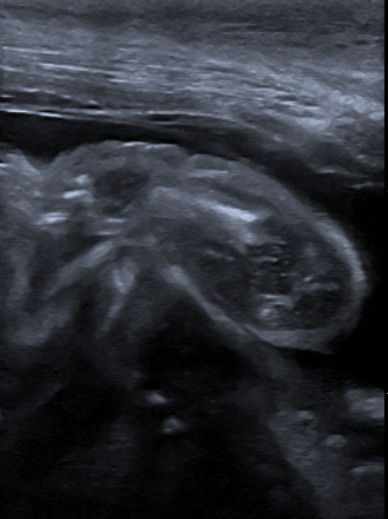

Kontrolne badanie USG pacjentki Weterynarii Dobieszowice. Serduszka biją prawidłowo, poród tuż tuż…..